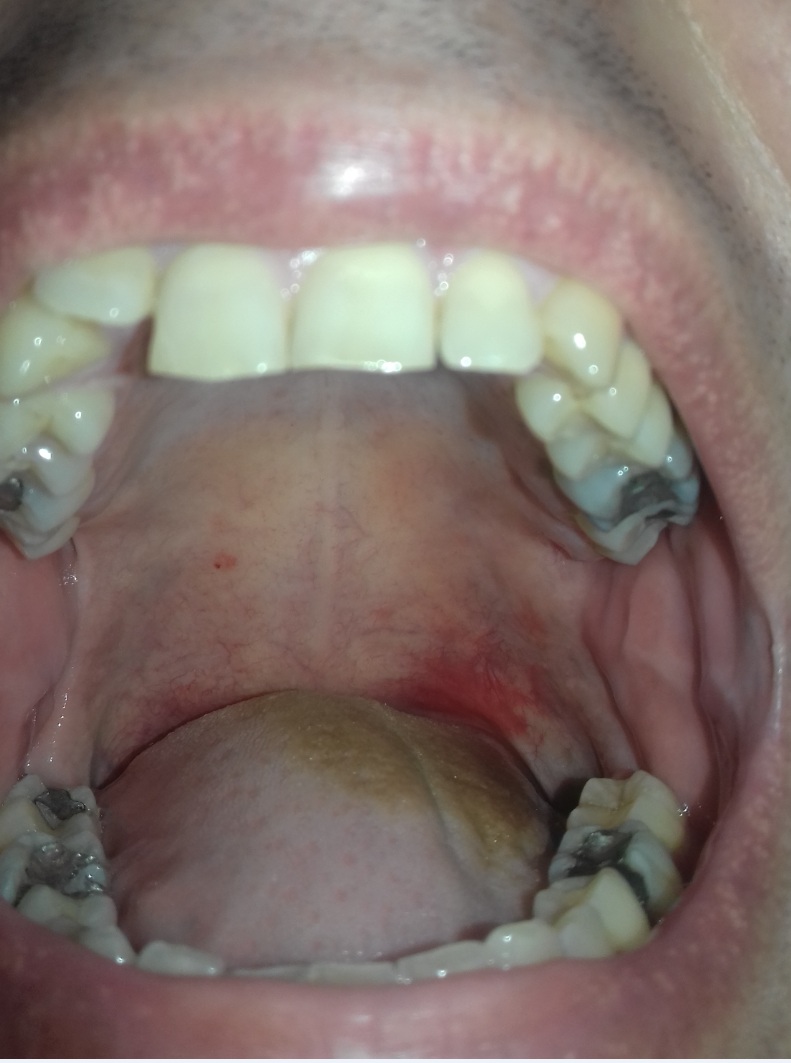

Behom asi 40 sekúnd po napľutí (zblízka hladiny vody) do pohára s vodou izbovej teploty (cca 20 stupňov) to v mojom prípade vyzerá takto...

sliny_2.jpg [ 258.56 KiB | Zobrazeno 13464 krát ]

A prečo som si spravil ten "slinový test" na candidu ? Pretože mám tieto príznaky (berte do úvahy, že si robím plno detoxu, cvičím, denne mám 16hod lačňovku, pijem až o 4hod po jedle, atď, proste samé zdravé návyky, takže nemám tých príznakov tak veľa ako bežný človek) :

Otázka na vás (pán Jarda, atď) .... zdá sa podľa foto a podľa príznakov ktoré som popísal, že budem mať tú kandidu premnoženú, že ? ...